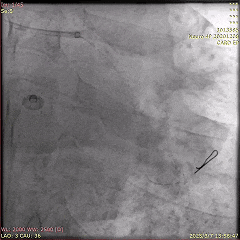

5天后,为患者进行第二次PCI,旨在处理LCx病变。冠脉造影显示,LCx中段模糊病变部位闭塞,术中于病变处植入药物洗脱支架,成功实现血管再通。

第二次PCI中的冠脉造影